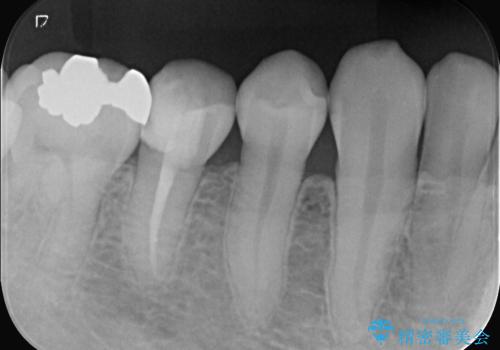

- 虫歯が大きく歯が欠けている状態でした。 そこに食べ物も詰まっている状態でした。

虫歯を除去後、精密根管治療を行い、オールセラミッククラウンで治療を行いました。

虫歯が大きく神経まで到達していました。将来根尖性歯周炎にならないよう徹底的に神経をとり洗浄したうえで被せ物をしています。